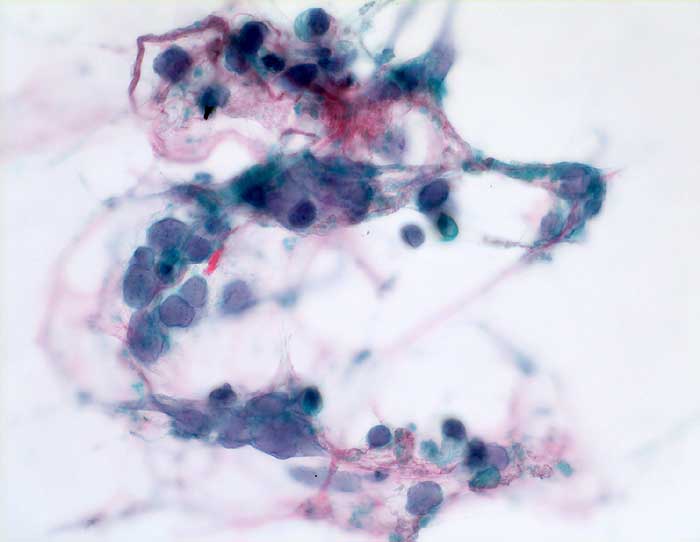

n/ Kleinzelliges Bronchuskarzinom

Kleinzelliges Bronchuskarzinom

Der Nachweis des kleinzelligen Karzinoms gelingt im Sputum meist leichter als im Bronchialsekret. Im Bronchialsekret sind die Tumorzellen oft zwischen Flimmerzellen und Entzündungszellen versteckt, während die stark hyperchromatischen Kerne im Sputum schon bei schwacher Vergrösserung ins Auge fallen. Die fast nacktkernigen Zellen liegen einzeln oder bilden schmale zeilenförmige Verbände und Haufen. Innerhalb der Verbände schmiegen sich die Kerne eng aneinander (=molding). Die Kerne sind zwei- bis dreimal so gross wie Lymphozyten. Im Sputum erscheinen die Karzinomzellen kleiner als im Feinnadelpunktat, Bürstenabstrich oder Bronchialsekret.

Basalzellen sind monomorpher und bilden kleine, regelmässige kompakte Verbände. Lymphomzellen liegen stets einzeln. Feindisperse Chromatinverteilung und zeilenförmige Verbände sprechen gegen ein Lymphom. In Zweifelsfällen erfolgt die Unterscheidung immunzytochemisch (Panzytokeratin und CD45).

Das ersten Beispiel zeigt ein Bronchialsekret, das zweite eine Bronchialbürstenzytologie.